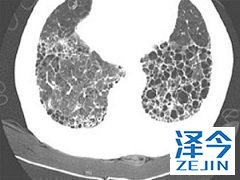

尼达尼布靶向药物抑制能够多种受体 尼达尼布可以用于治疗IPF,有多种靶向,包括受体酪氨酸激酶和非受体酪氨酸激酶。特发性肺纤维化是一种进程性疾病,患者患病后,肺功能会逐渐丧失,还可能出现呼吸困难的症状。那么尼达尼布治疗特发性肺纤维化的效果如何?多种靶向对治疗起到了哪些作用呢?

尼达尼布抑制以下RTKs:血小板衍生生长因子受体(PDGFR)α和β,成纤维细胞生长因子受体(FGFR)1-3,血管内皮生长因子受体(VEGFR)1-3和Fms样酪氨酸激酶-3 (FLT3)。 其中,FGFR,PDGFR和VEGFR与IPF发病机理有关。 尼达尼布与这些受体的三磷酸腺苷(ATP)结合口袋竞争性结合,并阻断细胞内信号传导,这对于代表IPF病理学的基本机制的成纤维细胞的增殖,迁移和转化至关重要。 此外,尼达尼布抑制以下nRTK:Lck,Lyn和Src激酶。 FLT3和nRTK抑制对IPF功效的贡献是未知的。

血管内皮生长因子(VEGF),成纤维细胞生长因子(FGF)和血小板衍生生长因子(PDGF)介导各种过程,包括纤维发生和血管生成,并且涉及IPF的发病机理。通过阻断底物结合和下游信号级联,尼达尼布干扰纤维化中活跃的过程,例如成纤维细胞增殖,迁移和分化,以及细胞外基质的分泌。